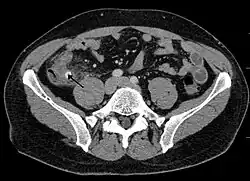

Computed tomography

Where it is readily available, computed tomography (CT) has become frequently used, especially in people whose diagnosis is not obvious on history and physical examination. Although some concerns about interpretation are identified, a 2019 Cochrane review found that the sensitivity and specificity of CT for the diagnosis of acute appendicitis in adults was high.[63] Concerns about radiation tend to limit use of CT in pregnant women and in children, especially with the increasingly widespread usage of MRI.[64][65]

The accurate diagnosis of appendicitis is multi-tiered, with the size of the appendix having the strongest positive predictive value, while indirect features can either increase or decrease sensitivity and specificity. A size of over 6 mm is both 95% sensitive and specific for appendicitis.[66]

However, because the appendix can be filled with fecal material, causing intraluminal distention, this criterion has shown limited utility in more recent meta-analyses.[67] This is as opposed to ultrasound, in which the wall of the appendix can be more easily distinguished from intraluminal feces. In such scenarios, ancillary features such as increased wall enhancement as compared to adjacent bowel and inflammation of the surrounding fat, or fat stranding, can be supportive of the diagnosis. However, their absence does not preclude it. In severe cases with perforation, an adjacent phlegmon or abscess can be seen. Dense fluid layering in the pelvis can also result, related to either pus or enteric spillage. When patients are thin or younger, the relative absence of fat can make the appendix and surrounding fat stranding difficult to see.[67]